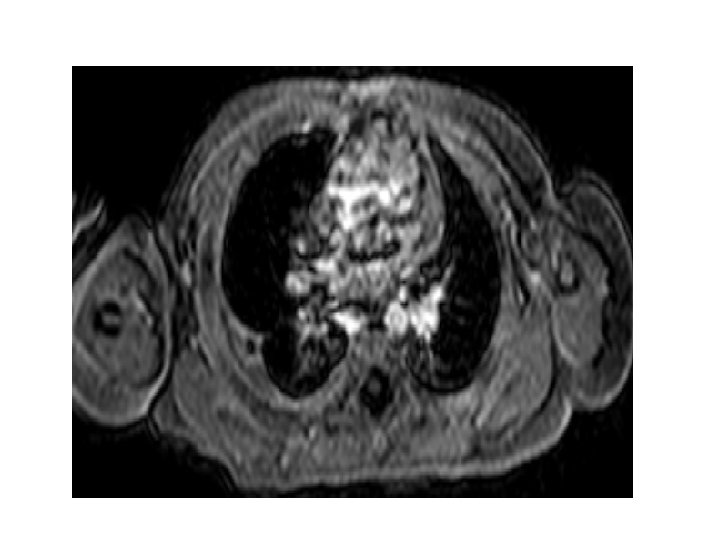

09/04/2013 Tarihli Toraks MR • Akciğer parankim alanlarının değerlendirilmesinde; aktif infiltratif görünüm ve nodüler lezyon saptanmadı. • Sağ akciğer alt lobda 9 x 14 mm boyutlu abse ile uyumlu içerisinde hava bulunan kalın duvarlı ve duvarı kontrast tutan kitle lezyon izlenmektedir. • Hastanın 26/03/2013 tarihli toraks BT incelemesine göre boyutları küçülmüştür. • Ayrıca sağdaki plevral efüzyon gerilemiştir. • Sağ akciğer alt lob posteriorda hafif konsolide görünüm izlenmekte olup, 26/03/2013 tarihli incelemeye göre gerilemiştir.

24/04/2013 Tarihli Toraks MR • 09. 04. 2013 tarihli MR incelemede sağ akciğer alt lobda izlenen kalın duvarlı abse ile uyumlu lezyon günümüz MR incelemesinde belirgin derecede küçülmüş olup çapı 1 cm ölçüldü. • Sağda bu alan komşuluğunda plevrada fokal kalınlaşma ve minimal plevral efüzyon izlenmektedir. • Sağ akciğer alt lob posteriorda hafif konsolide görünüm izlenmekte olup, 26/03/2013 tarihli incelemeye göre gerilemiştir.

12/05/2013 Tarihli Toraks MR • 24/04/2013 tarihli MR incelemede sağ akciğer alt lobda tanımlanan abse lezyon günümüz MR incelemesinde gerilemiş olup bu lokalizasyonda sekel değişiklikler mevcuttur.